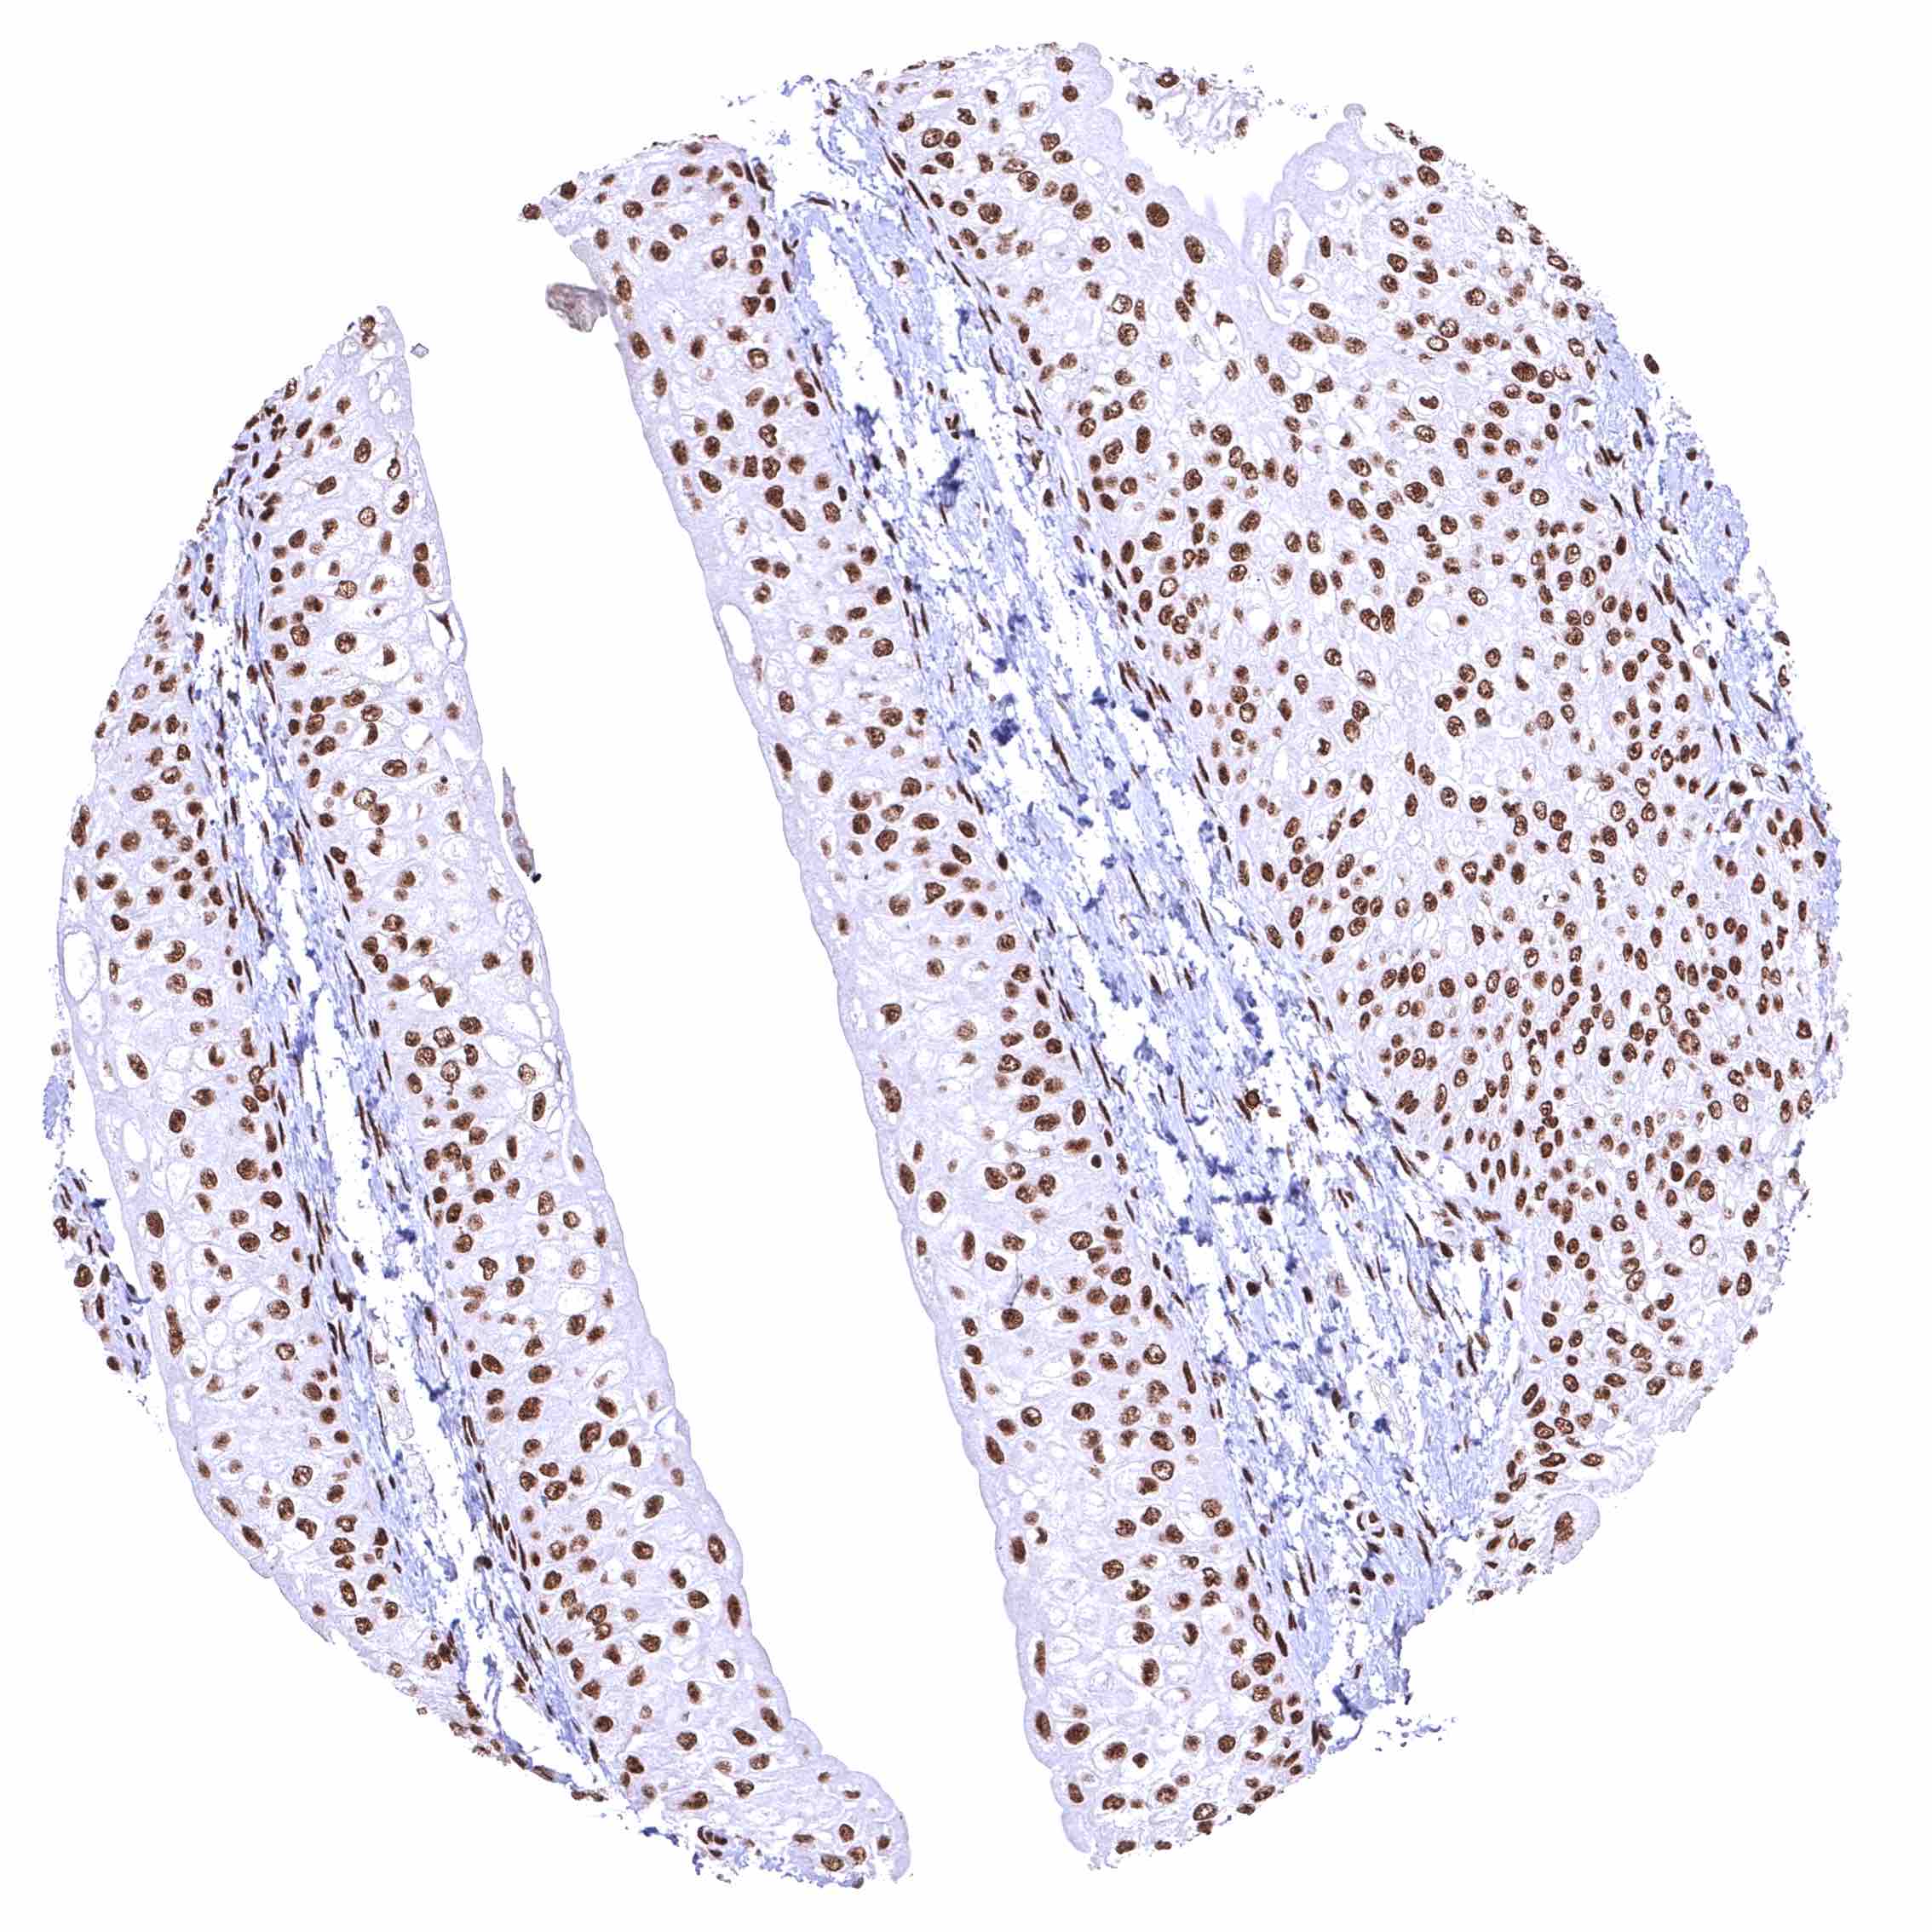

Skeletal muscle – Distinct nuclear BRD4 staining of all cells. The additional cytoplasmic staining of some muscle cells may represent an antibody specific cross-reactivity.

Skeletal muscle – Distinct nuclear BRD4 staining of all cells. A cytoplasmic staining of muscle cells is not seen in this sample.